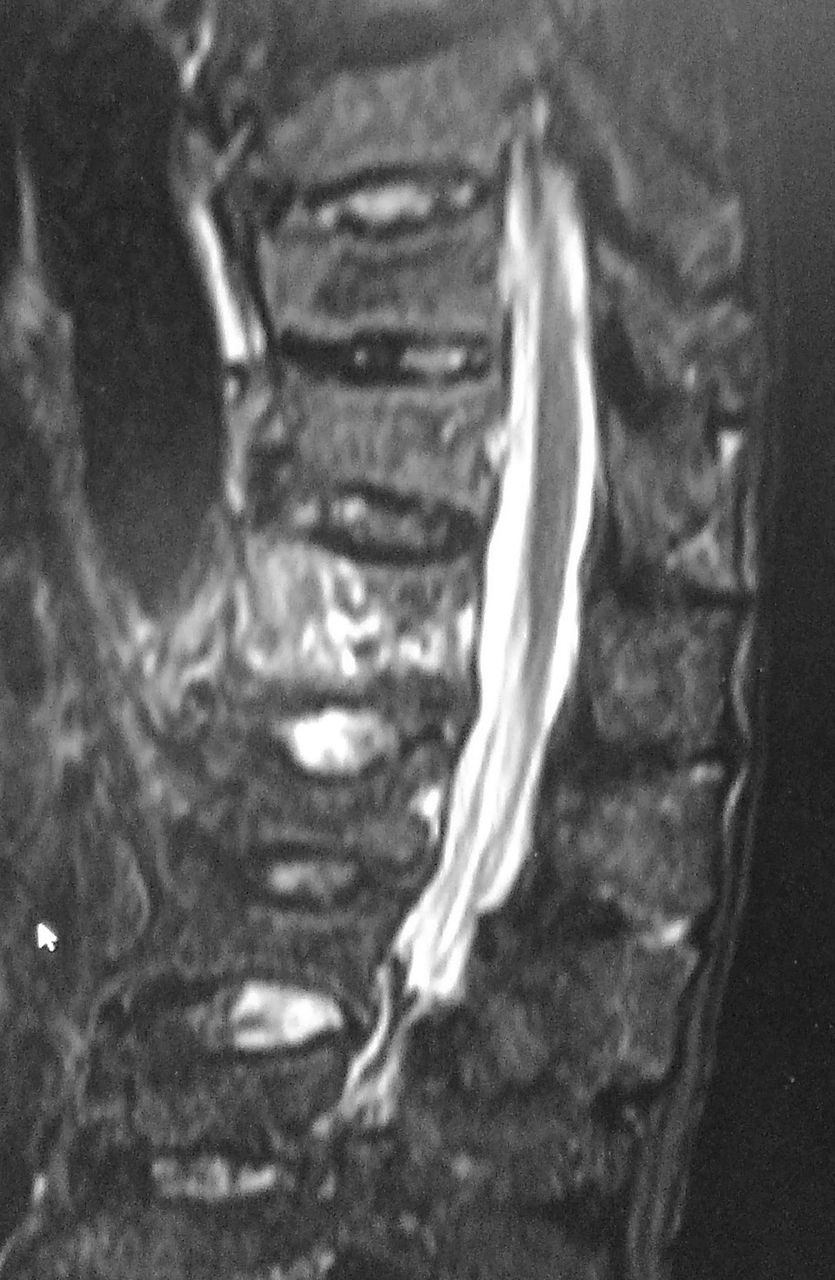

びまん性特発性骨増殖症 Dish 山田 賢太郎 本来は小さな骨が連なっている脊椎が 一本の骨になってしまうdishの有無を見極め 手術に工夫を凝らしています 堀 悠介 脊椎の手術がより正確で安全にできるよう 術前計画を入念に行っています

保存的治療で治癒したびまん性特発性骨増殖症に生じた高度転位を伴う頚椎損傷の1例 臨床雑誌整形外科 69巻13号 医書 Jp

ユジカワ 整形dr イラストレーター On Twitter 簡単に言えばそれぞれの椎体が繋がる病気 椎体がそれぞれ分かれて動かないため 長管骨のように働いてバキッという折れ方をすることがある また 日頃からそれぞれの椎体にかかる荷重が減ることも 骨質の低下に

びまん性特発性骨増殖症 Dish に伴う胸椎骨折が原因で大量血胸をきたした2例 整形 災害外科 64巻7号 医書 Jp